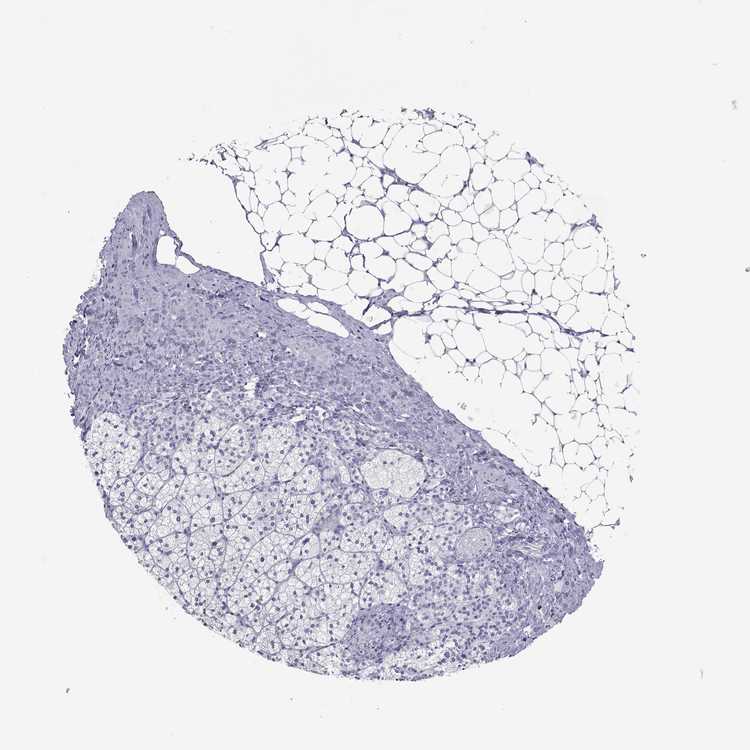

TISSUE PRIMARY DATA ADRENAL GLAND Show tissue menu

ADRENAL GLAND - Antibody stainingi

Antibody staining in the annotated cell types in the current human tissue is reported as not detected, low, medium, or high, based on conventional immunohistochemistry profiling in selected tissues. This score is based on the combination of the staining intensity and fraction of stained cells.

Each image is clickable and will lead to virtual microscopy that enables deeper exploration of all samples and also displays staining intensity scores, fraction scores and subcellular localization as well as patient and tissue information for each sample.

Antibody HPA052219

Glandular cells Not detected